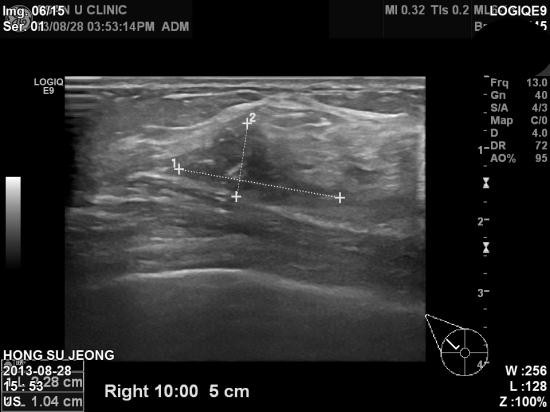

올해 공단검진에서 시행한 유방촬영상 이상소견으로

본원에 의뢰된 만48세 여자분이십니다.

우측 유방에 두개의 혹이 인접하여 있어 조직검사를 실시하여

두군데 다 유방에 잘 생기는 침윤성 유관암이 진단되셨습니다.